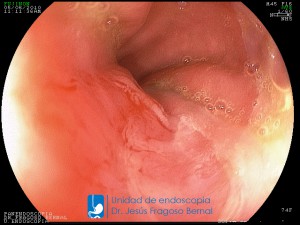

La Unidad de Endoscopía fue creada en 2002 por el Dr. Jesús Fragoso Bernal, es pionera en el estado por la utilización de la tecnología más avanzada, que nos permite ofrecer servicios integrales de diagnóstico y tratamiento para las enfermedades del aparato digestivo.